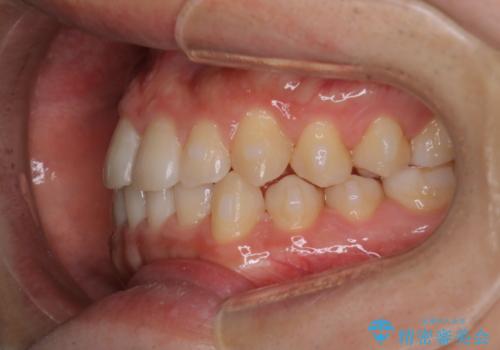

- 前歯のがたつきを主訴に来院されました。初診時、右上2番の口蓋側転位と右下7番の舌側傾斜が認められました。

インビザラインにてIPRと歯列弓拡大を行い、ゴム掛けで噛み合わせを改善する治療計画を立てました。

マウスピースの使用時間が短いため、シュミレーション通り進むか不安でしたが

治療期間1年で、主訴である前歯のがたつきを改善出来、

奥歯の噛み合わせも良くなりました。